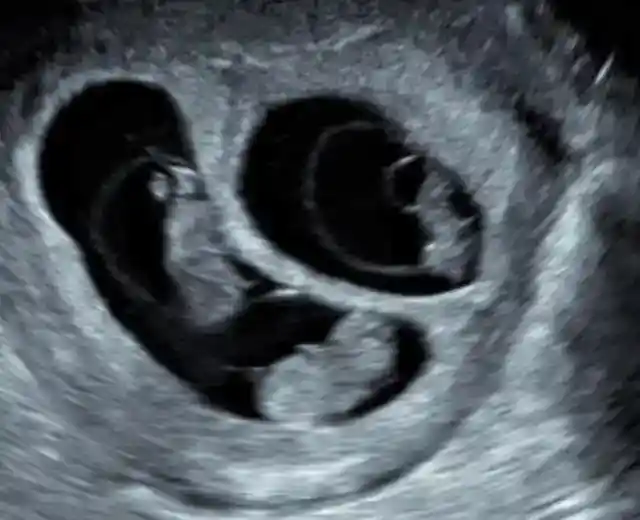

It was due to the fact that she was not only expecting one baby.

Angie was pregnant with three. Just imagine she needed to carry three babies at once!

As for two of the babies in Angie’s womb, they were sharing one placenta.

The fact that there was only one placenta for two babies was not really a major problem, but it certainly had its disadvantages for the babies.

The size of one baby was going to be hampered and it wouldn’t get to be the same size as the other babies in Angie’s belly. Nevertheless, there were a lot of other possible complications which were listed, which this problem paled in comparison with.